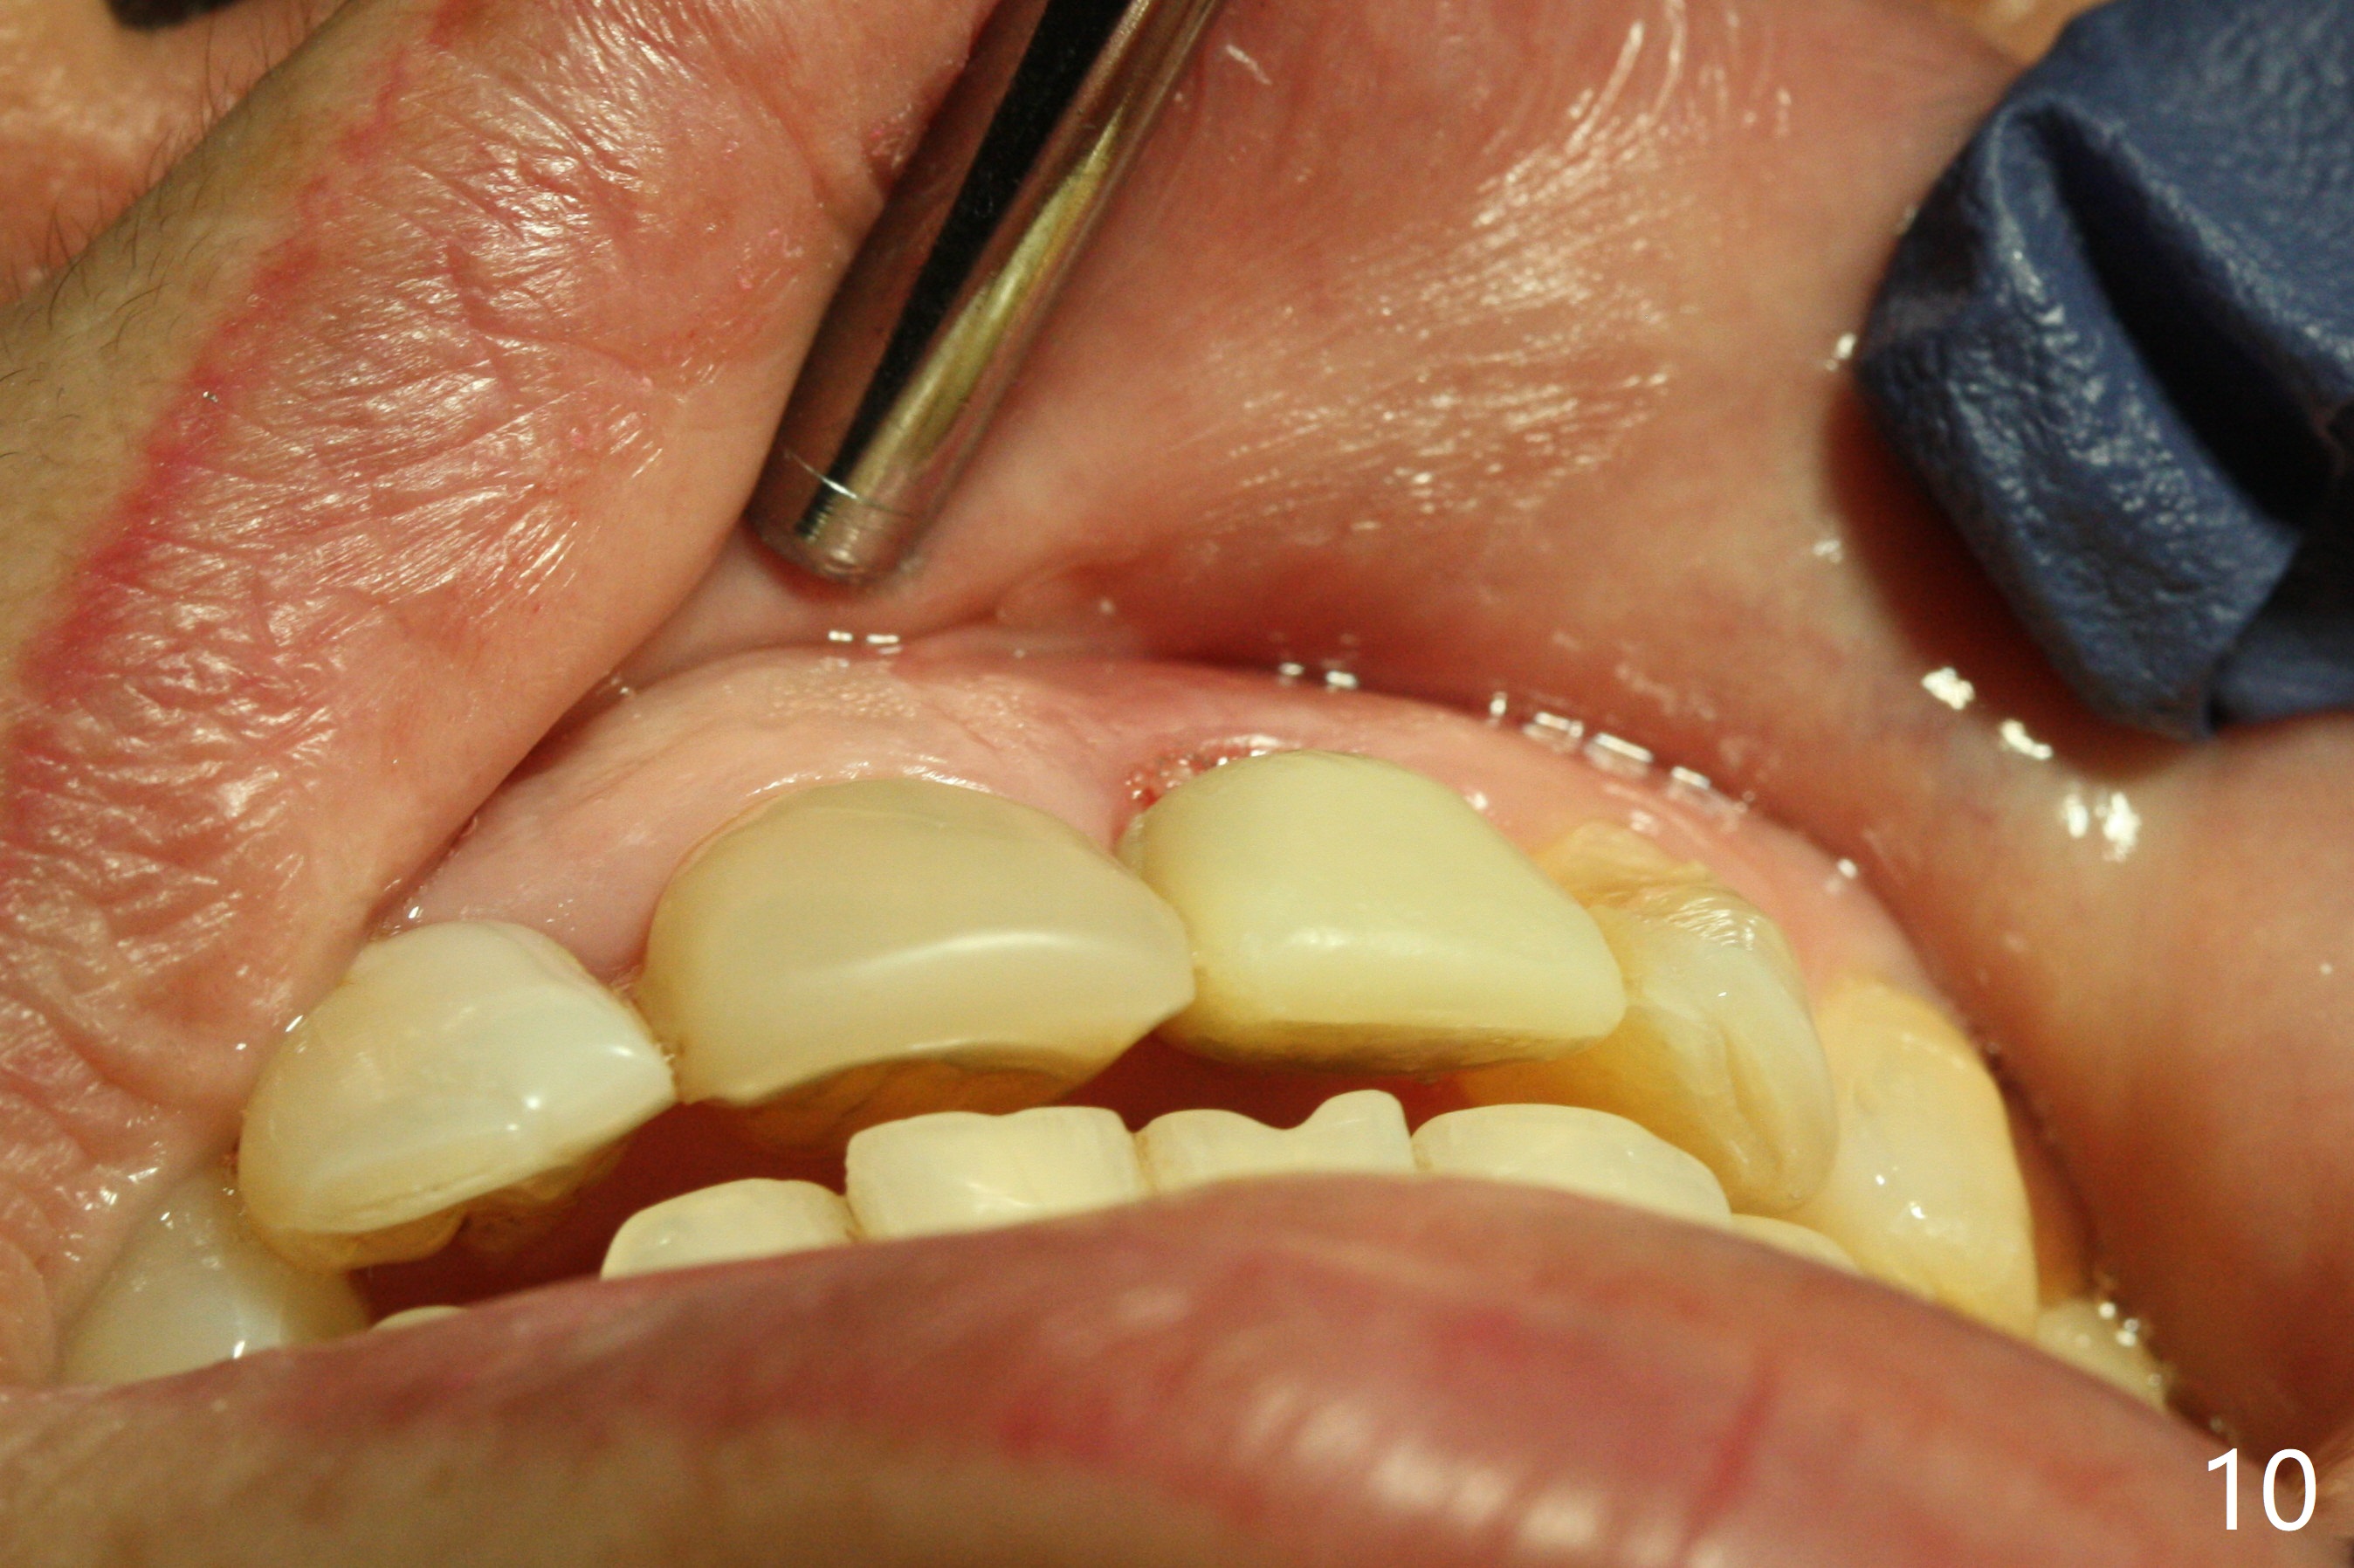

In spite of the incisobuccal shift of the tooth #9 with gingival recession (Fig.1) and loss of the buccal plate (intraop finding), there is no buccal contour collapse (Fig.2 *), due to the presence of the buccal bone of the neighboring teeth and the root of the affected tooth. After extraction, osteotomy (Fig.3) and dummy implant try in (Fig.4), a definitive implant is placed palatally with the buccal gap (Fig.5 *). In fact there is mild buccal contour collapse prior to bone graft (Fig.5 arrow). When allograft (Vera, Fig.6,7 *) is packed buccal to the implant and overlying abutment as a solid support, the buccal contour seemingly returns normal (Fig.6 arrowhead). An immediate provisional is fabricated to prevent loss of the bone graft during healing period. Bone graft kept in place by the provisional turns yellow 6 days postop (Fig.8). The buccal plate remains strong, while the fistula becomes indistinguishable. After adjustment of the provisional margin a few times (nearly 3 months postop, Fig.9,10), the gingival margin appears to have grown incisally, as compared to Fig.1. There is minimal buccal bone collapse (Fig.10). Dislodgement of the abutment and provisional forces her to return 1 year 4 months postop; the socket has healed (Fig.11). The buccal plate is not concave 1 year 4 months postop (Fig.12). The gingiva is slightly recessive (Fig.13) with mild buccal plate concavity (Fig.14) immediately before cementation. The implant could be placed ~ 1 mm deeper (Fig.15).